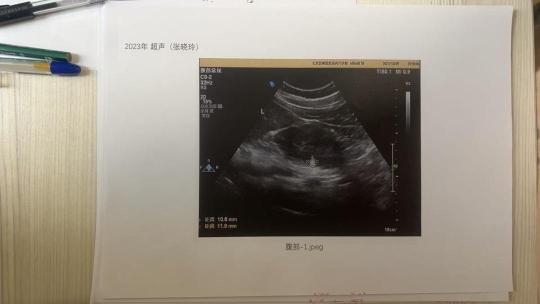

张晓玲称,爱康国宾提供的超声影像无姓名、ID等信息。(受访者供图)

张晓玲对爱康国宾提供的影像图片提出了异议。